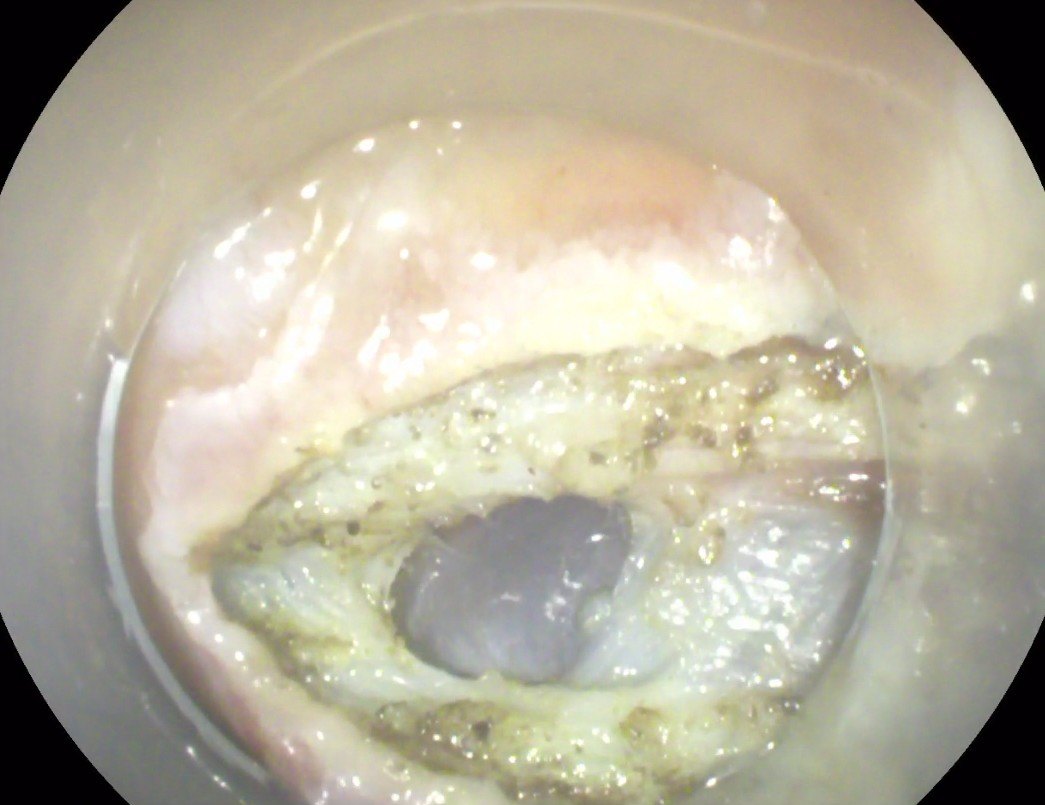

经口胃镜下肝囊肿开窗术 - 好大夫在线

图片尺寸1043x809